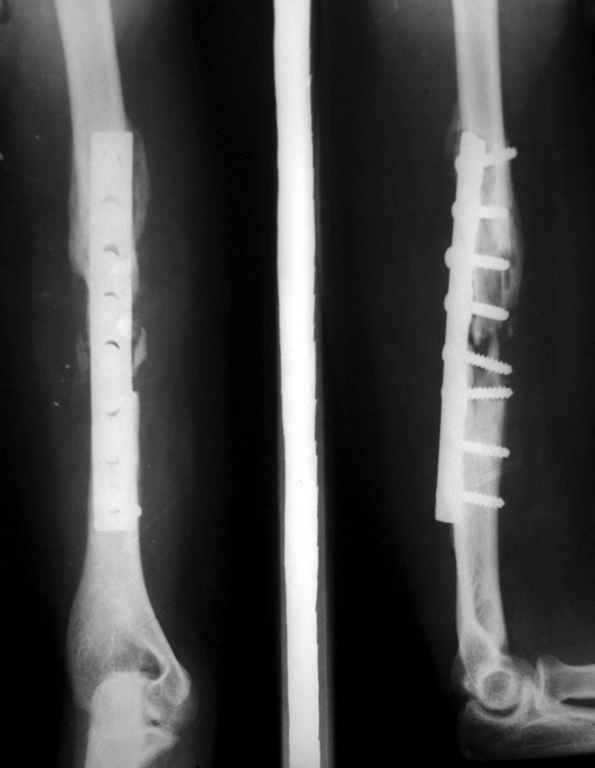

убрать железо,скусить склерозированную кость с места пеерлома, реостеосинтез нормальным блокированным гвоздем максимального диаметра, хороший контакт между фрагментами ( не бояться укорочения плеча), место перелома обложить спонгиозным аутотрансплантатом из грубня подвздойной кости

Здравствуйте г. Шевченко! В данном случае мне думается,что необходима свободная костная пластика аутотрансплантатом из фрагмента малоберцовой кости на микрососудистых анастомозах с накостным остеосинтезом. Использование некровоснабжаемого костного трансплантата чревато лизисом последнего. Спасибо. С уважением профессор Валеев (г, Уфа).

Владимир. Выделяем свои малоберцовую кость практически полность. Выпиливаем замок там и тут. Синтез. Нетипичный случай, но перестраивается хорошо даже диафиз. С уважением Дрягин

Коллеги, др Виталий Дрягин представил отличное наблюдение. Аутотрансплантат в случае достижения абсолютной стабильности при лечении ложных суставов плеча работает отлично! Другой способ пластики так же с достижением абсолютной стабильности я представил в теме под названием "Результат консервативного лечения короткого косого перелома диафиза плеча врачами общей практики в условиях развивающейся страны у больного low social class"